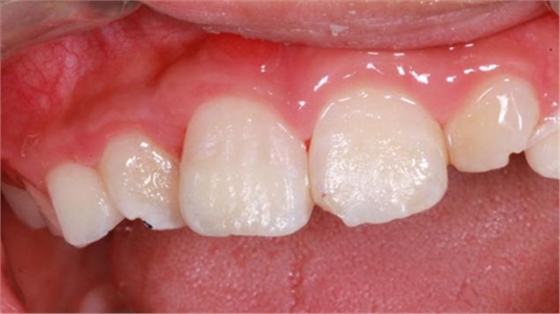

最后附一例樹(shù)脂關(guān)閉牙間隙的病例。具體操作不做詳細(xì)描述。

術(shù)前如下:

術(shù)后即刻如下圖:

術(shù)后5小時(shí)復(fù)查如下圖: